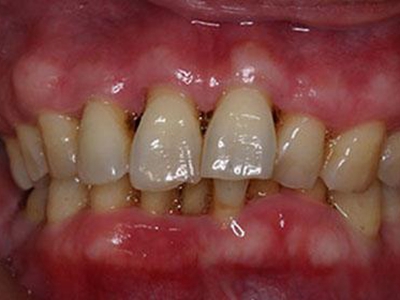

慢性龈炎又称边缘性龈炎或单纯性龈炎,主要表现为游离龈和龈乳头因炎性水肿,而变为鲜红或暗红色,龈缘变厚,龈乳头圆钝肥大。慢性龈炎的患病率高,治愈后仍可复发,部分患者可发展成为牙周炎。

慢性龈炎的病损部位一般局限于游离龈和龈乳头,以前牙区为主,尤其以下前牙区最为显著,患者常因刷牙或咬硬物时牙龈出血而就诊。游离龈和龈乳头颜色变为鲜红或暗红色,病变较重时炎性充血可波及附着龈。龈缘变厚,龈乳头圆钝肥大,可增生呈球状,覆盖牙面。牙龈松软脆弱,缺乏弹性。

当牙龈以增生性反应为主时,龈缘和龈乳头呈坚韧的实质性肥大,质地较硬而有弹性。龈沟液量增多,还可能出现龈沟溢脓现象。